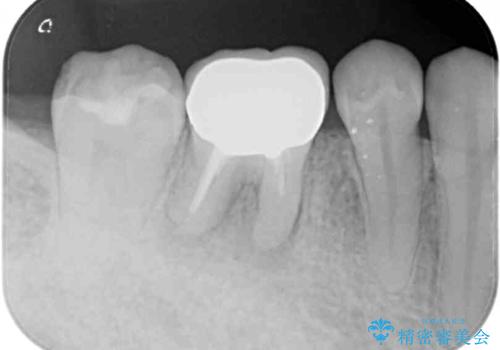

- 歯肉の退縮に伴い、金属を用いたクラウンの縁が見えてしまうことを気にして来院された患者様です。

歯肉には膿の出口が見られ、レントゲン写真からは歯根周辺に病変が認められたため、まずは根管治療を行い、その後フルジルコニアクラウンにて補綴することとしました。